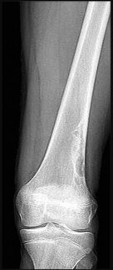

Figures 13a and 13b are the radiographs of a 57-year-old man who is seen in the emergency department. He has been experiencing left thigh pain for 2 month. Four years ago he underwent laparoscopic nephrectomy and states that he has been disease free since the resection (although he has not seen a doctor in 2 years). The pathogenesis of osteolysis in renal cell carcinoma metastatic to bone includes secretion of parathyroid hormone-related peptide (PTHrP), transforming growth factor-B (TGF-B), and vascular endothelial growth factor (VEGF), which directly cause overexpression receptor activation of nuclear factor kB ligand (RANKL) on which cells?

Tumor cells in renal cell carcinoma interact with the bone microenvironment to drive bone destruction and tumor growth by secreting factors such as PTHrP, TGF-B, and VEGF. These factors stimulate the host osteoblast, causing overexpression of RANKL, which in turn causes bone resorption through stimulation of osteoclasts. RANKL expression is upregulated in many types of metastatic cancer to bone, and blocking the RANK/RANKL interaction prevents progression of metastases.

Other actions of RANKL include triggering the migration of human tumor cells that express RANK. RANK and RANKL are expressed in metastatic renal cell carcinoma, and their presence strongly signifies potential recurrence. The use of denosumab, which binds and inactivates RANKL, has its basis in these findings in renal cell carcinoma.